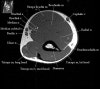

2. Axial section

1) The tendons of the Biceps Brachii and Brachiallis muscles transversely as they insert onto the Radius and Ulna respectively. 2) The distal Triceps tendon is also well evlauated in this plane.